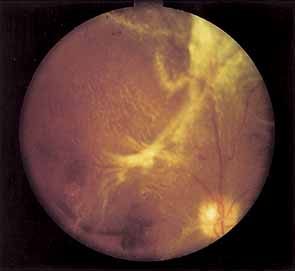

Two types of diabetic retinal detachments occur, those that are caused by traction alone (nonrhegmatogenous) (Fig. 14), and those caused by retinal break formation (rhegmatogenous) (Figs. 15 and 16). Characteristics of nonrhegmatogenous (traction) detachment in PDR include the following: (1) the detached retina is usually confined to the posterior fundus and infrequently extends more than two-thirds of the distancd to the equator, (2) it has a taut and shiny surface, (3) it is concave toward the pupil, and (4) there is no shifting of subretinal fluid.

Fig. 14 Traction retinal detachment. The detached retina has a smooth noncorrugated appearance and is convex toward the pupil.

Fig. 15 Combined traction/rhegmatogenous retinal detachment. The detached retina has a corrugated appearance and is concave toward the pupil.

In combined traction/rhegmatogenous detachment, the borders of the elevated retina usually extend to the ora serrata; the retinal surface is dull and grayish and undulates because of retinal mobility caused by shifting subretinal fluid. The causative retinal breaks are usually found in the posterior pole near areas of fibrovascular proliferation. They are oval in shape and appear to be partly the result of tangential traction from the proliferative tissue as well as vitreous traction. Determining the location of retinal holes may be complicated by many factors, particularly poor dilation of the pupil, lens opacity, increased vitreous turbidity, vitreous hemorrhage, intraretinal hemorrhage, and obscuration of the breaks by overlying proliferative tissue. Often they are only located during vitrectomy surgery.